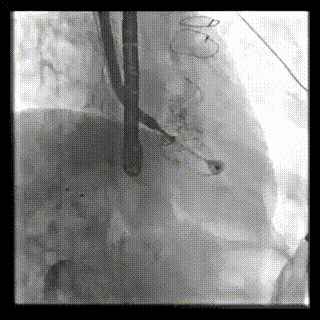

本周三例接受LuX-Valve Plus經(jīng)血管三尖瓣置換術(shù)的患者中,第一例患者為冠狀動(dòng)脈旁路移植術(shù)+Bentall+二尖瓣成形術(shù)后;第二例患者為永久起搏器植入術(shù)后,存在跨三尖瓣導(dǎo)線;第三例患者合并房顫、房缺及左心耳封堵術(shù)后。

三例患者入院后,葛均波院士團(tuán)隊(duì)周達(dá)新教授、潘文志教授、張?jiān)床┦俊㈥惿┦考靶某业呐舜湔浣淌凇⒗顐ソ淌趯?duì)患者的情況進(jìn)行詳細(xì)評(píng)估和討論,最終決定為三例患者選擇LuX-Valve Plus40mm、50mm和50mm型號(hào)的瓣膜進(jìn)行手術(shù)治療。手術(shù)后即刻拔除氣管插管,術(shù)后患者三尖瓣反流癥狀得到顯著改善,復(fù)查心超結(jié)果顯示人工三尖瓣瓣膜支架固定穩(wěn)定,瓣葉關(guān)閉形態(tài)未見異常,未見明顯反流。